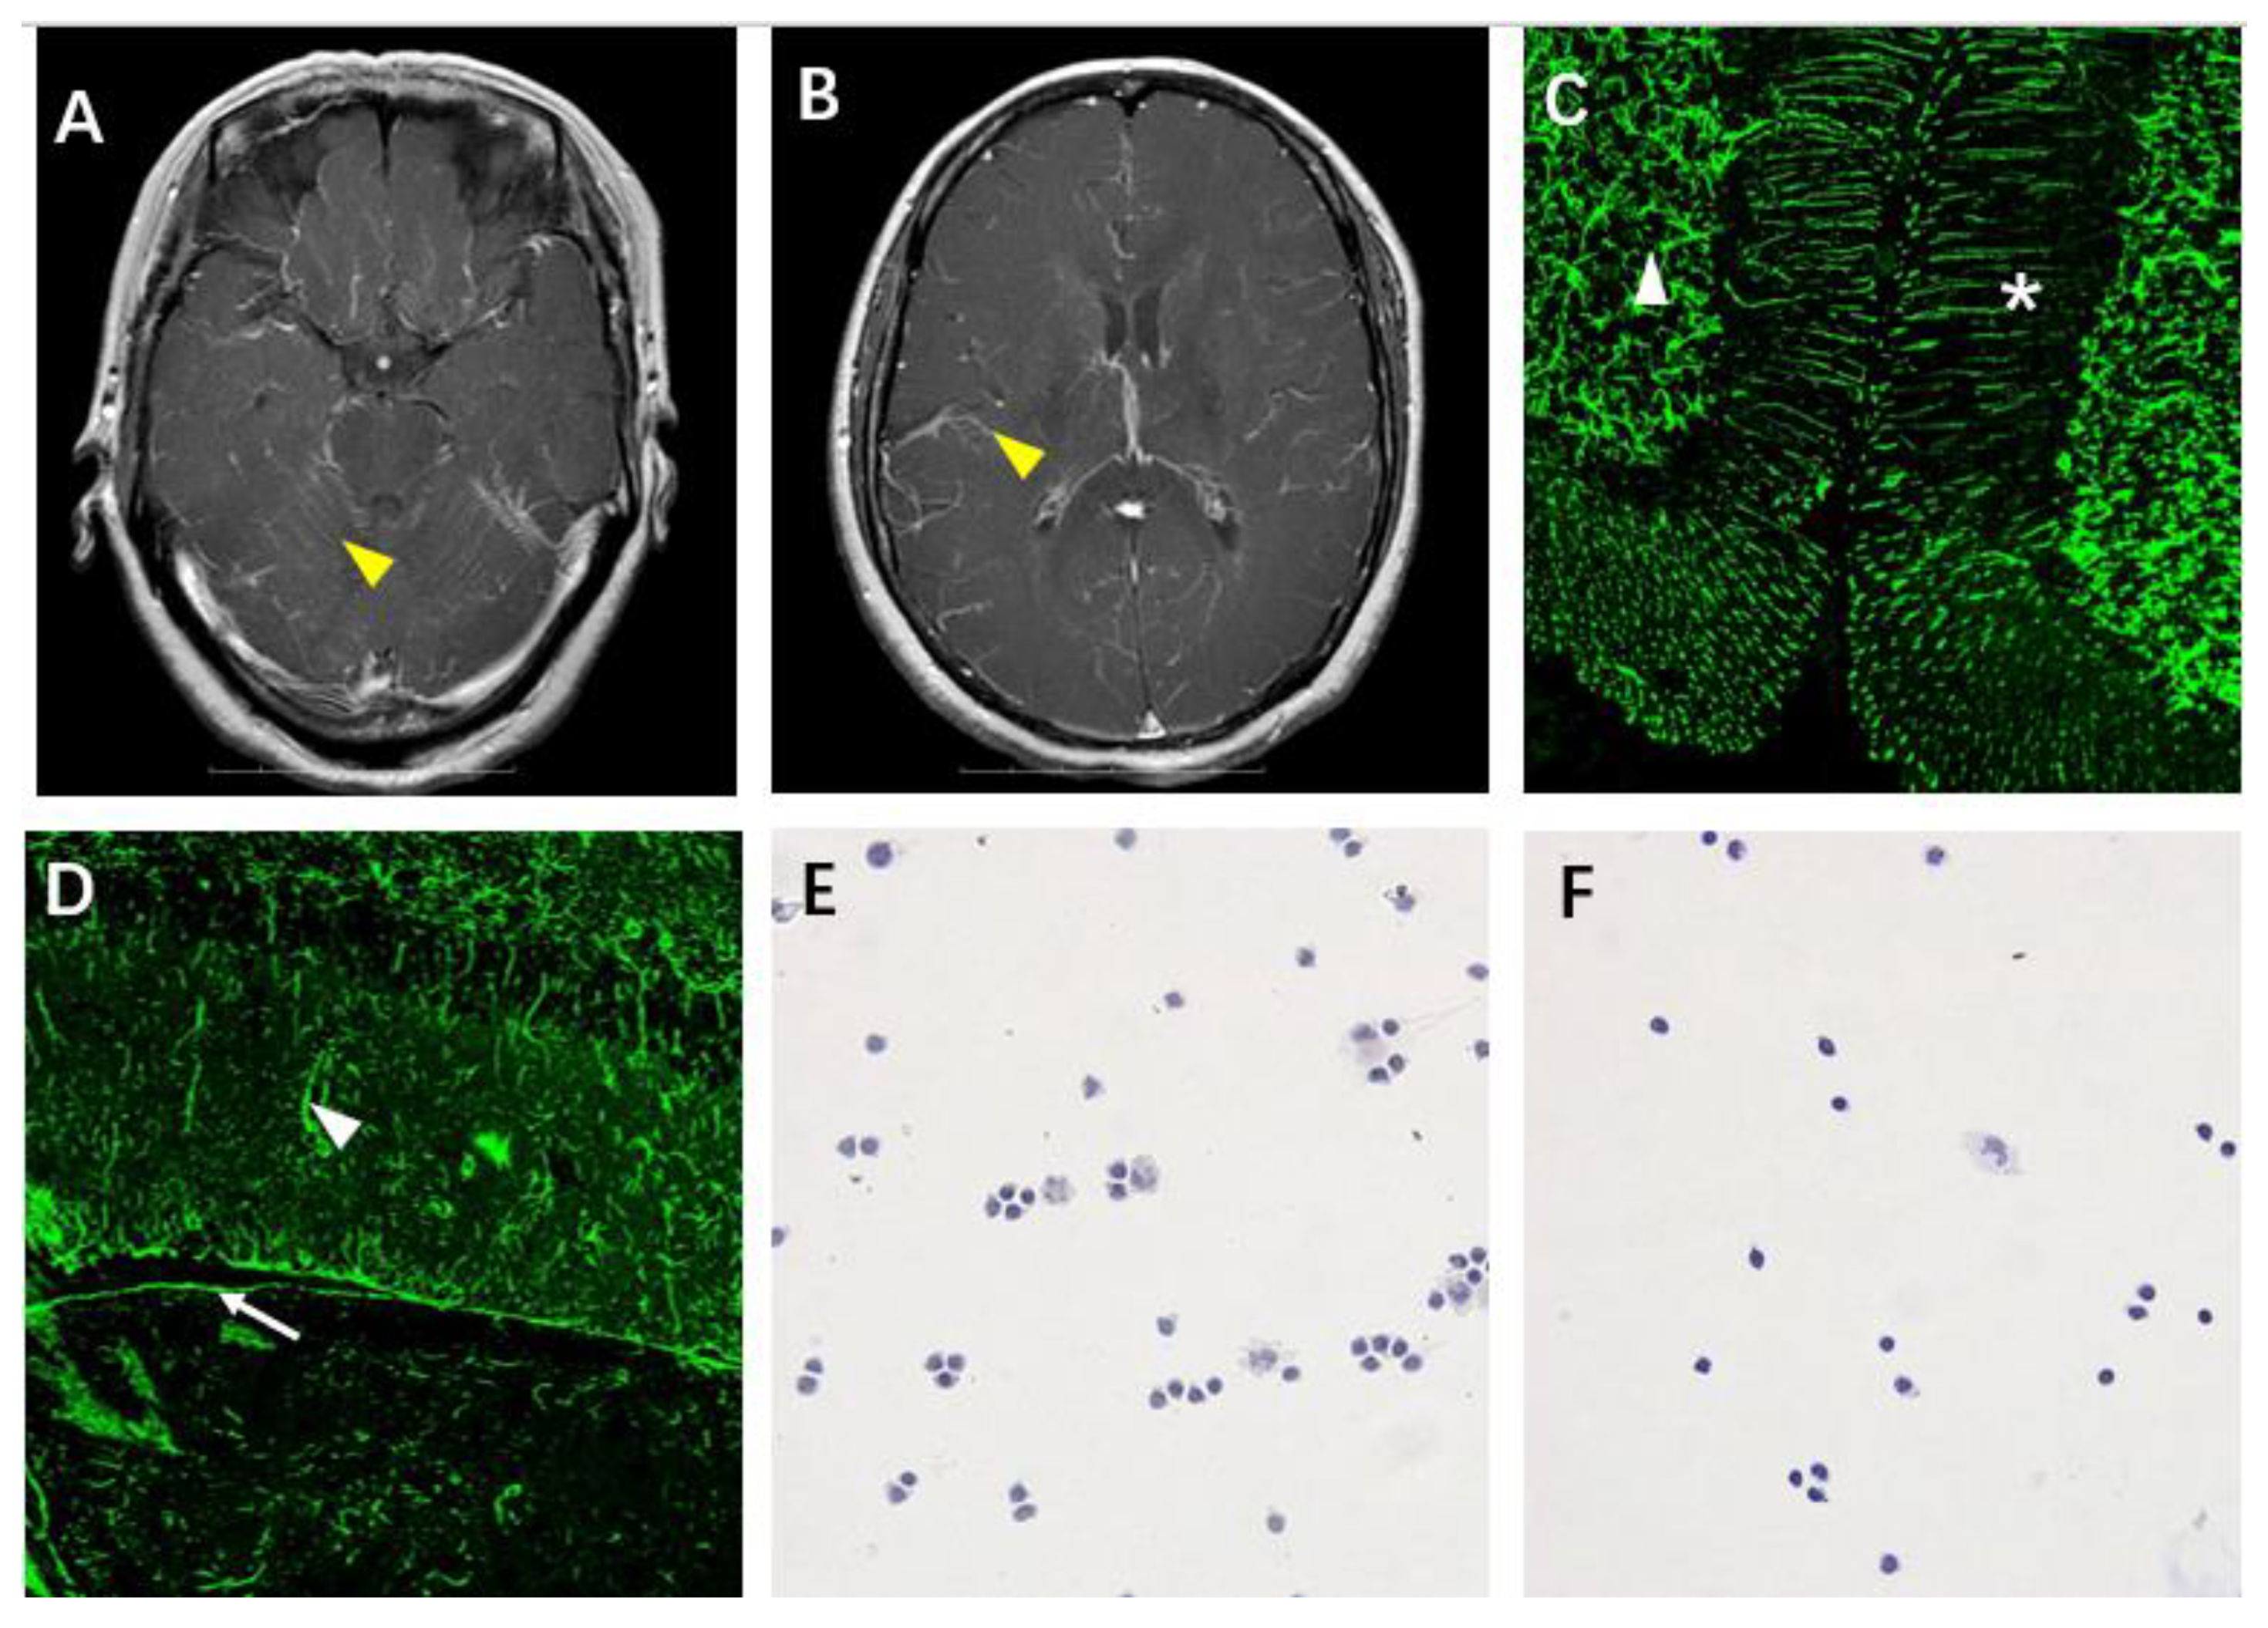

4.1. Case 2

4.2. Case 3